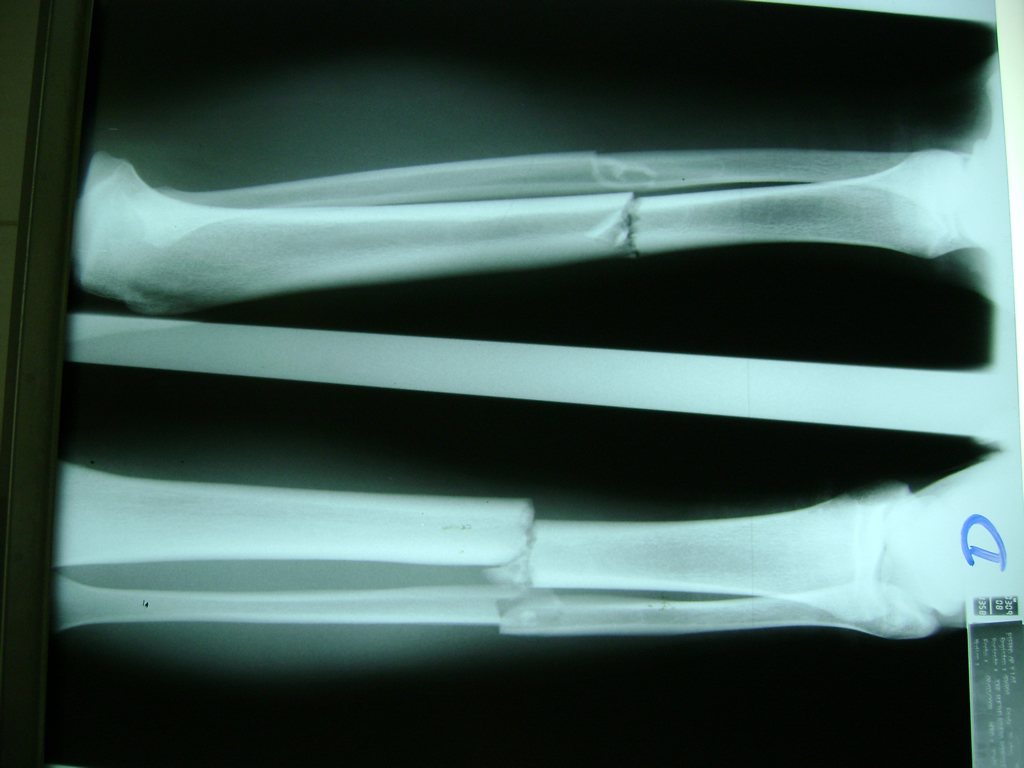

Cirugías de Tobillos

Aunque cada uno de estos huesos puede fracturarse por separado, normalmente la rotura es una lesión que se produce de forma conjunta

La mayor parte de las roturas implican a la parte proximal del hueso (parte del hueso próximo a la rodilla) o a la parte distal (parte del hueso cerca del tobillo).

Debido a la fina cobertura de piel que recubre la tibia y el peroné, las fracturas generalmente son abiertas, es decir, el hueso roto rasga la piel, atravesándola. Las fracturas de tibia y peroné generalmente se producen por un fuerte impacto o torsión.